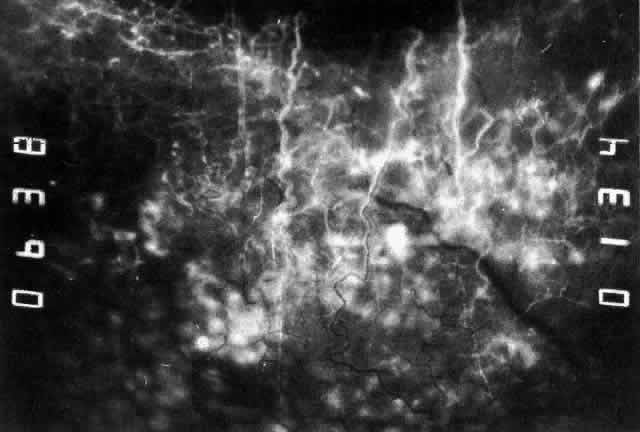

The characteristic features of necrotizing scleritis on fluorescein angiography are hypoperfusion and, eventually, nonperfusion of the vascular networks (Figs. 40 through 43).26 The initial changes are on the venous side of the capillary network; the transit time of the dye increases even if the eye is red and congested. If the disease process persists or has been present for a long time, thrombosis and permanent vaso-occlusive changes occur. These vessels (or the occluded capillary network) are bypassed by the opening of anastomotic channels. New vessels in a granuloma give rise to deep intrascleral leakage of dye (see Fig. 43). Conjunctival and episcleral involvement by the destructive change is late but is always preceded by vaso-occlusive changes that can sometimes be detected with use of the red-free light on the slit lamp (Figs. 44 and 45).